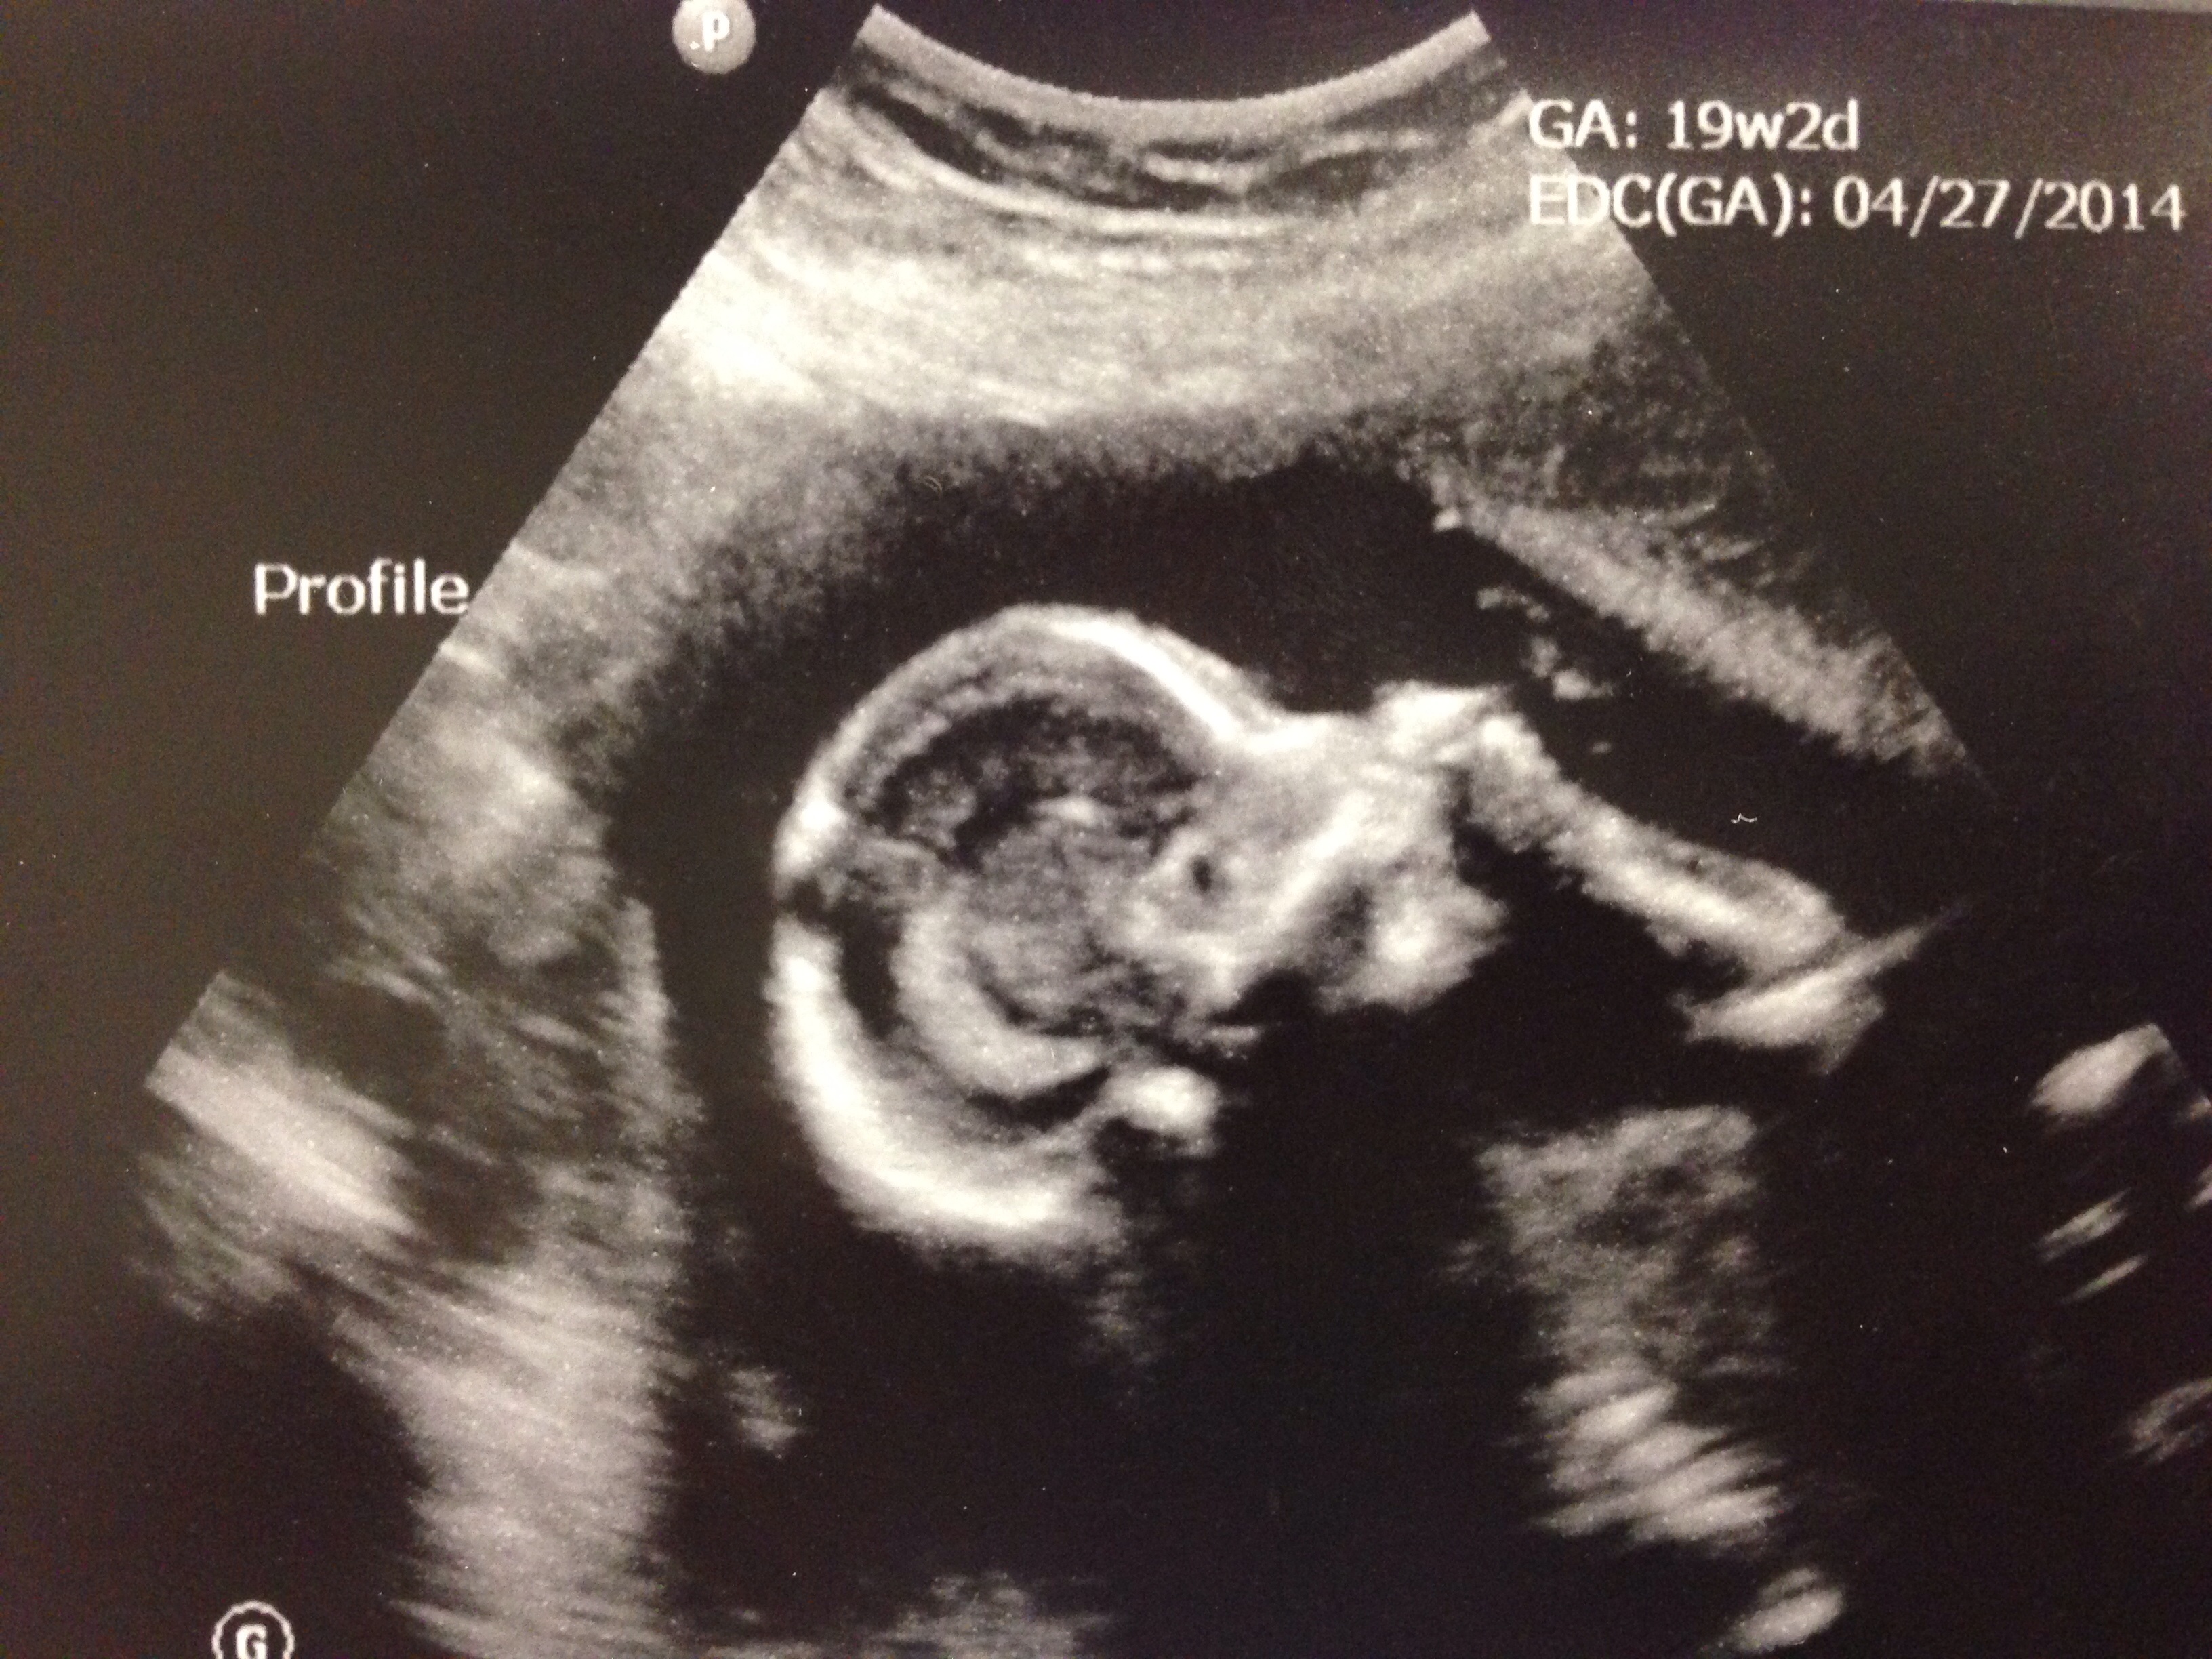

image

Married my love 10/18/08 | DS born 07/16/11 | MMC 01/16/13 at 11w6d | DD edd 04/27/14